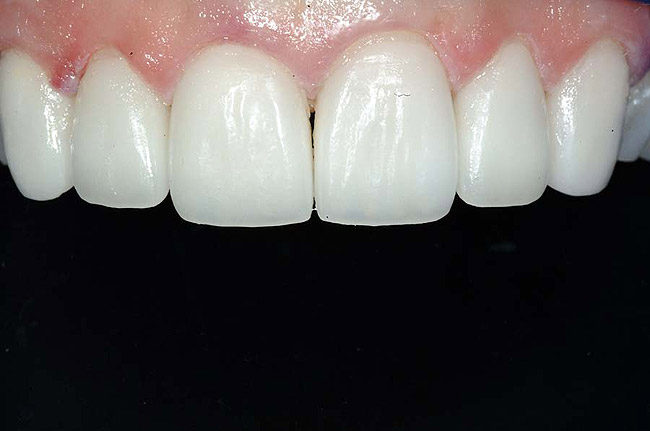

For example, before initiating the cementation process, preparations must be thoroughly cleansed (Figure 3), and adequate hemostasis and isolation should be ensured (Figure 4). Although newer generations of adhesives have been shown to be more tolerant of saliva contamination,7 proper isolation and hemostasis are still advisable because saliva and blood contamination cannegatively influence the bond strength of some bonding systems.8,9 Also,consider that resin cements are preferred for esthetic restorations, including porcelain laminate veneers.10,11 Successful use of these cements is dependent upon the incorporation of proper ceramic conditioning and tooth-surface treatment (ie, multiple-step total etch or self-etch adhesive)(Figure 8');" rem="#ip:figure5 through Figure 8">Figure 5 through Figure 8) to avoid incompatibility issues with the chosen cement and/or enhance the mechanical interlocking that occurs between the porcelain/resin-cement/tooth interfaces.10-13

Figure 3 At the cementation appointment, the provisional restorations were removed, and the teeth were thoroughly cleaned.